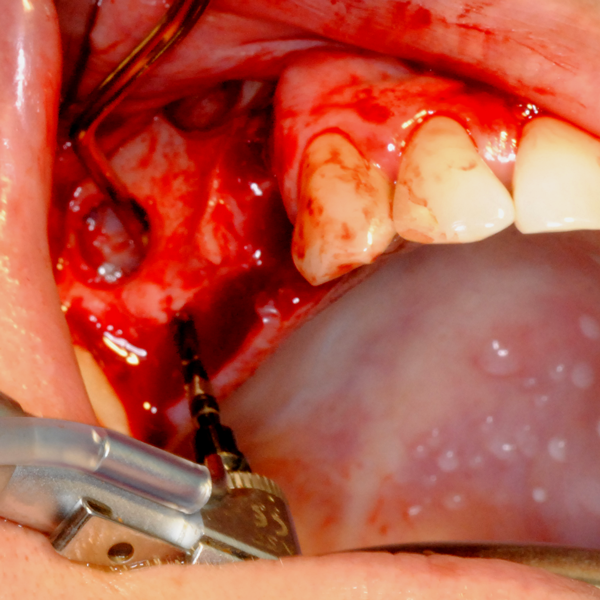

Отворен максиларен синус в началото на интервенцията. Случаят е интересен със следното - твърде атипична форма на трепанационния отвор. На какво се дължи на това - на лошо планиране на оперативния достъп или на нещо друго? Дължи се на факта, че отначало въпросната намеса беше планирана като балонен синуслифт; за съжаление обаче мембраната на синуса се разкъса и надуването на балона стана невъзможно.